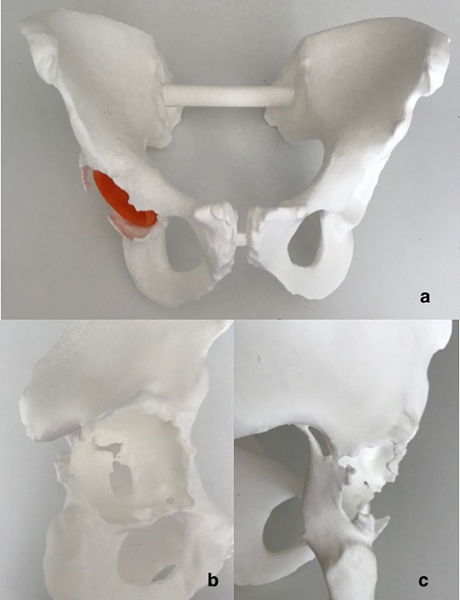

使用Materialize Mimics軟件根據(jù)CT掃描數(shù)據(jù)創(chuàng)建骨盆的3D數(shù)字模型。通過分割,骨骼與周圍的軟組織和患者的假體有所區(qū)別。

3:使用3D建模軟件制作的三維圖像。 (a,b)保留髖臼杯的整個骨盆。在分割過程中股骨和股骨干被去除。 (cd)骨質(zhì)量圖顯示了具有正常骨質(zhì)量的區(qū)域(綠色)和具有低骨質(zhì)量和厚度的區(qū)域(紅色)。

e,f)骨缺損區(qū)域和骨折擴(kuò)展的測量。

“第一階段是閾值化,其中包括密度在Hounsfield UnitHU)值的指定范圍內(nèi)的所有體素。為了排除金屬和陶瓷植入物,包括松質(zhì)骨和皮質(zhì)骨,我們使用了HU范圍為1301750的面罩。最后的分割,去除了軟組織和偽影,是使用軟件的其他工具手動執(zhí)行的(圖3ab)。最終,從相應(yīng)的骨盆中以數(shù)字方式去除股骨和金屬植入物,并創(chuàng)建了孤立的目標(biāo)區(qū)域(ROI)的3D圖像?!备鶕?jù)各個區(qū)域的皮質(zhì)和整體骨厚度,將具有顏色梯度的骨質(zhì)量圖用于髖臼。隨后分析了骨折的面積,形狀和空間位置,以及“與對側(cè)髖臼相比,髖臼骨丟失和旋轉(zhuǎn)中心”。最后,在Form 3L系統(tǒng)上3D打印了患者整個骨盆的真人大小模型。

4:(a)整個骨盆的3D打印真人大小的塑料模型。 (b,c)特別是內(nèi)壁和后柱骨折。